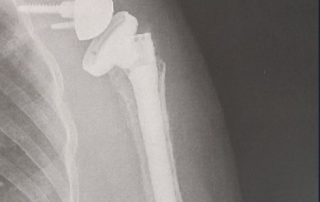

While working on a construction site, Mr. G’s foot was run over by a piece of heavy equipment causing him to fracture a bone in his foot into multiple fragments (comminuted fracture [...]